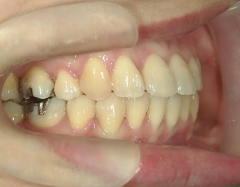

矯正歯科(全顎ワイヤー矯正)治療後

矯正歯科 治療後